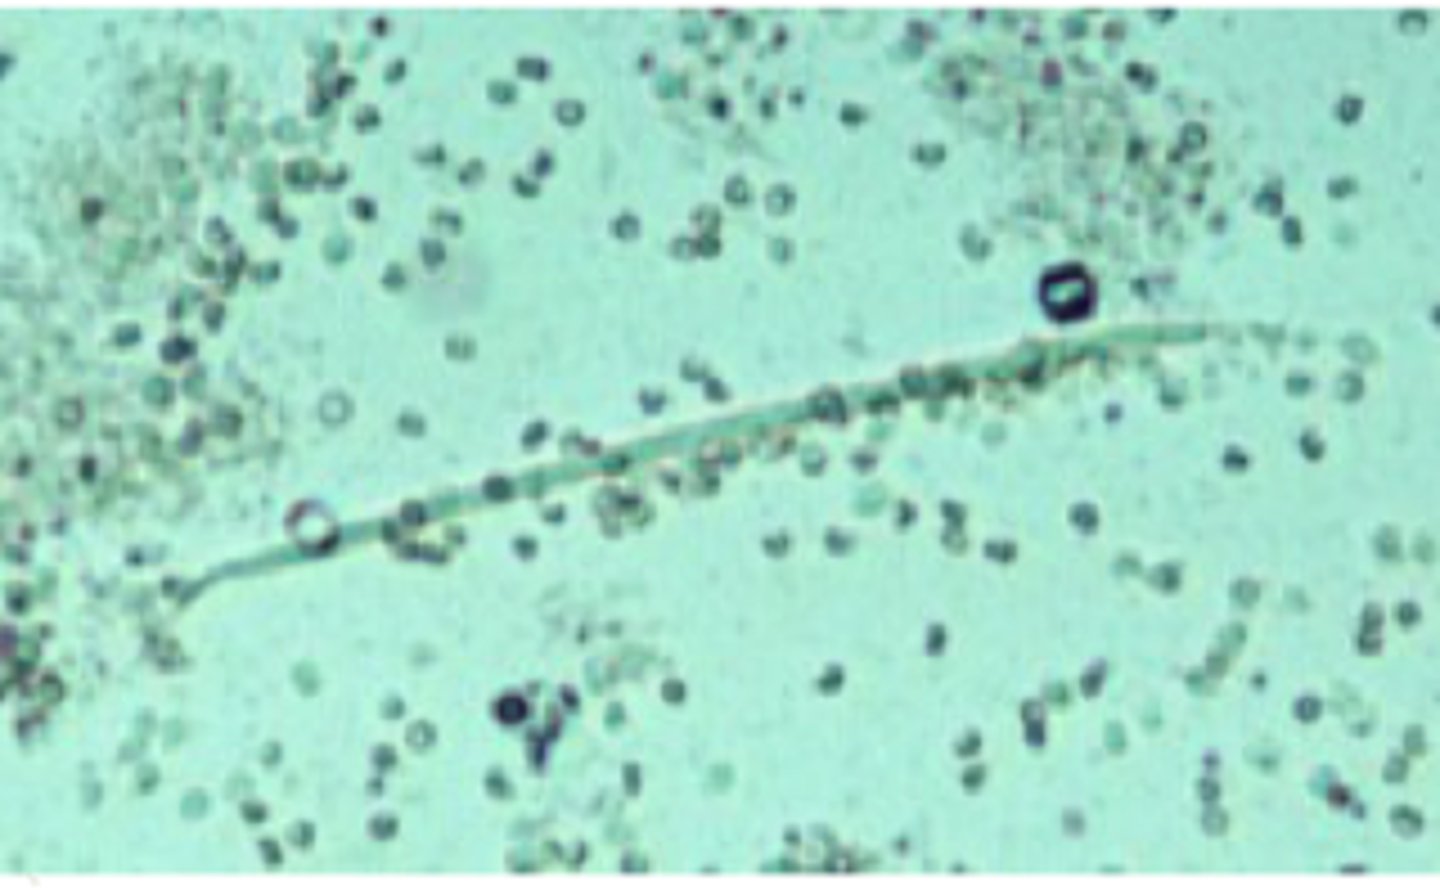

microfilaria

urine

microfilaria